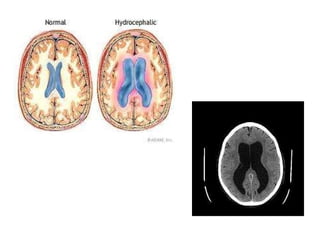

Hydrocephalus An abnormal increase in the volume of CSF Symptoms:  sleep changes, spastic paresis, papilledema, bulging of skull in young, seizures, cranial nerve deficits, depression.

Hydrocephalus Communicating  –  due to excessive formation of CSF or lack of absorption Non-communicating –  due to obstruction of flow through ventricle system

Hydrocephalus An abnormalincrease in the volume of CSF Symptoms: sleep changes, spastic paresis, papilledema, bulging of skull in young, seizures, cranial nerve deficits, depression.